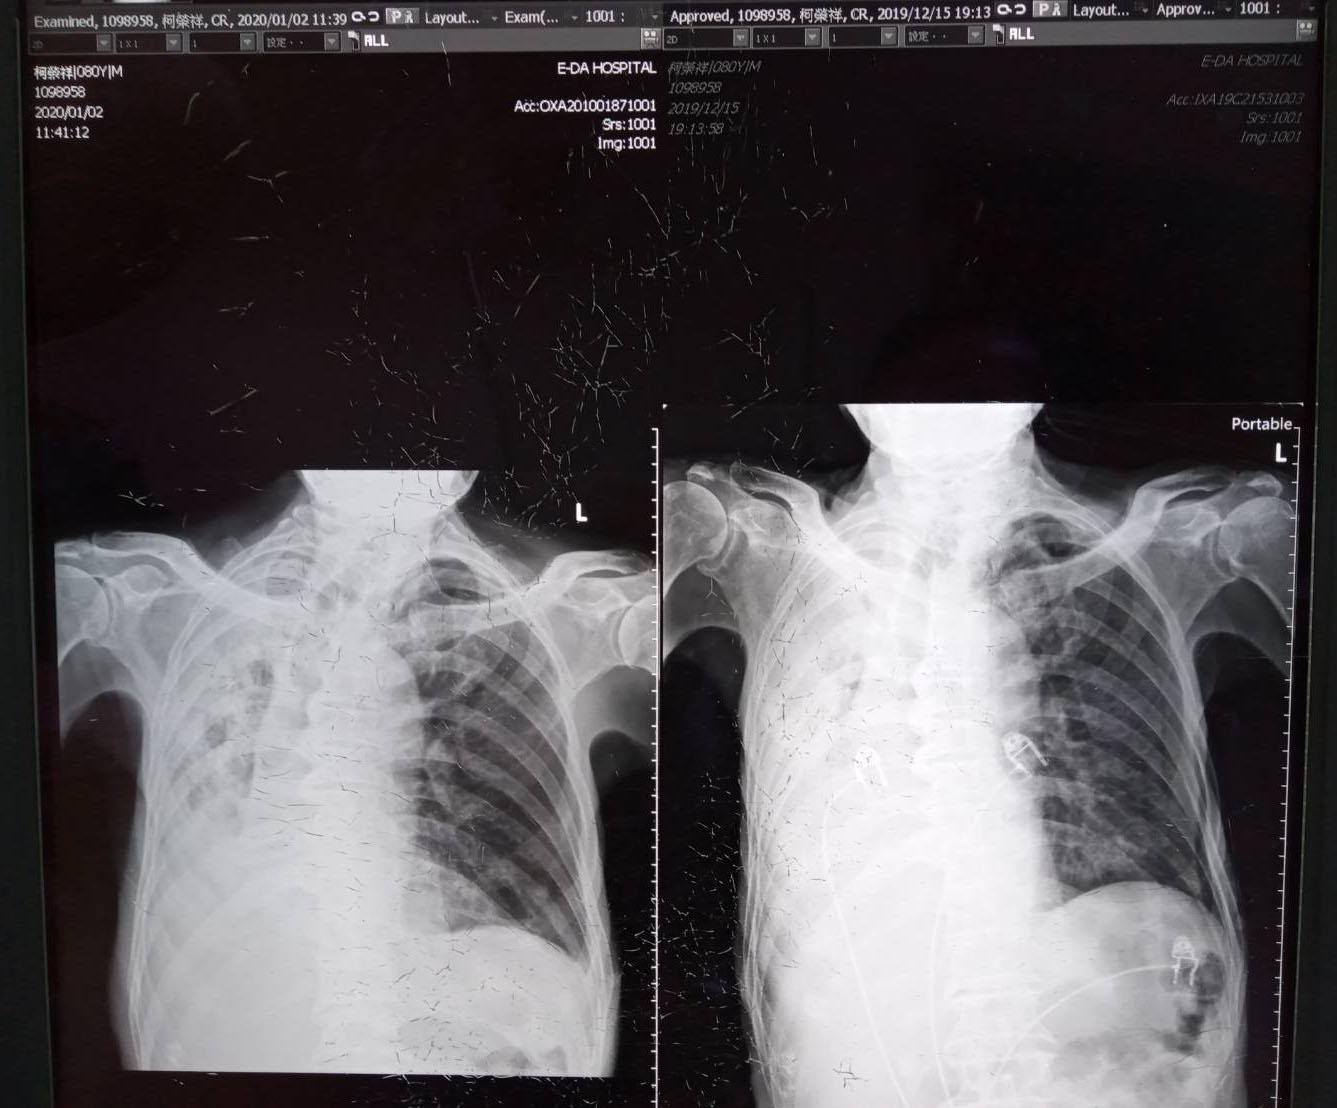

隔天起來,父親仍在。我知道師父幫了一個大忙。父親不但沒走,還一天一天好起來,醫生都覺的驚奇,到12月27日,醫生還宣佈父親可以出院。實在是太神奇了,醫生叫我一月二日回診。回診那天,又照了X光,我請醫生把兩張X光照片併起來拍,醫生同意,拍給了我,右邊是生死存亡的那天(2019.12.15),左邊是回診那天拍的(2020.1.2),可以發現左肺有明顯改善。

回診日和最危險那天的X光